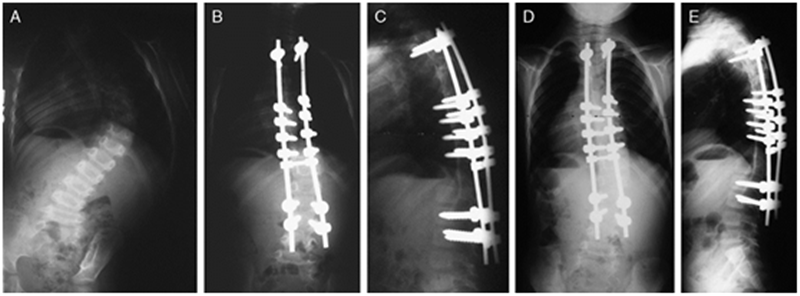

2.2 Shilla技术

Shilla系统包括矫形棒、单向和万向的椎弓根螺钉。在顶椎区予以4对螺钉有限融合,上下端椎予以带滑槽的椎弓钉,该系统允许脊柱沿棒的两端生长。

2010年,McCarthy[13]于11例动物模型中应用Shilla技术治疗,结果显示:平均的生长长度为48mm,解剖仅观察到微小的磨损但无断钉断棒等;McCarthy[14]于2014年又报道了38例行Shilla技术治疗的患者,术后3个月予以支具保护,随访2年以上(图 3),术前Cobb角平均为70.5°,术后6周为27°;2年随访示肺容量改善13%,躯干高度(C7-S1)增长12%,出现了3例棒相关并发症,2例感染。

2017年,Luhmann等[15]多中心回顾性比较了Shilla系统和生长棒系统,结果表明二者在并发症率上无明显差异,且Shilla技术在畸形的矫正与矫形效果的维持上更有优势。同时Shilla手术创伤更小,手术次数少3-4倍。但Shilla系统对于置钉要求较高,钉棒易出现无法滑动的状态。

Shilla技术适合特发EOS,Cobb>50°,单或双弯(柔韧性好)患儿,主要并发症在于金属反应及内固定失败等。

图7 McCarthy等[14]报道了38例行Shilla技术治疗的患者,随访2年以上。A:3岁婴儿特发性脊柱侧凸患儿术前正位X片;B和C为术后3月影像资料;D和E为术后2年正侧位X片